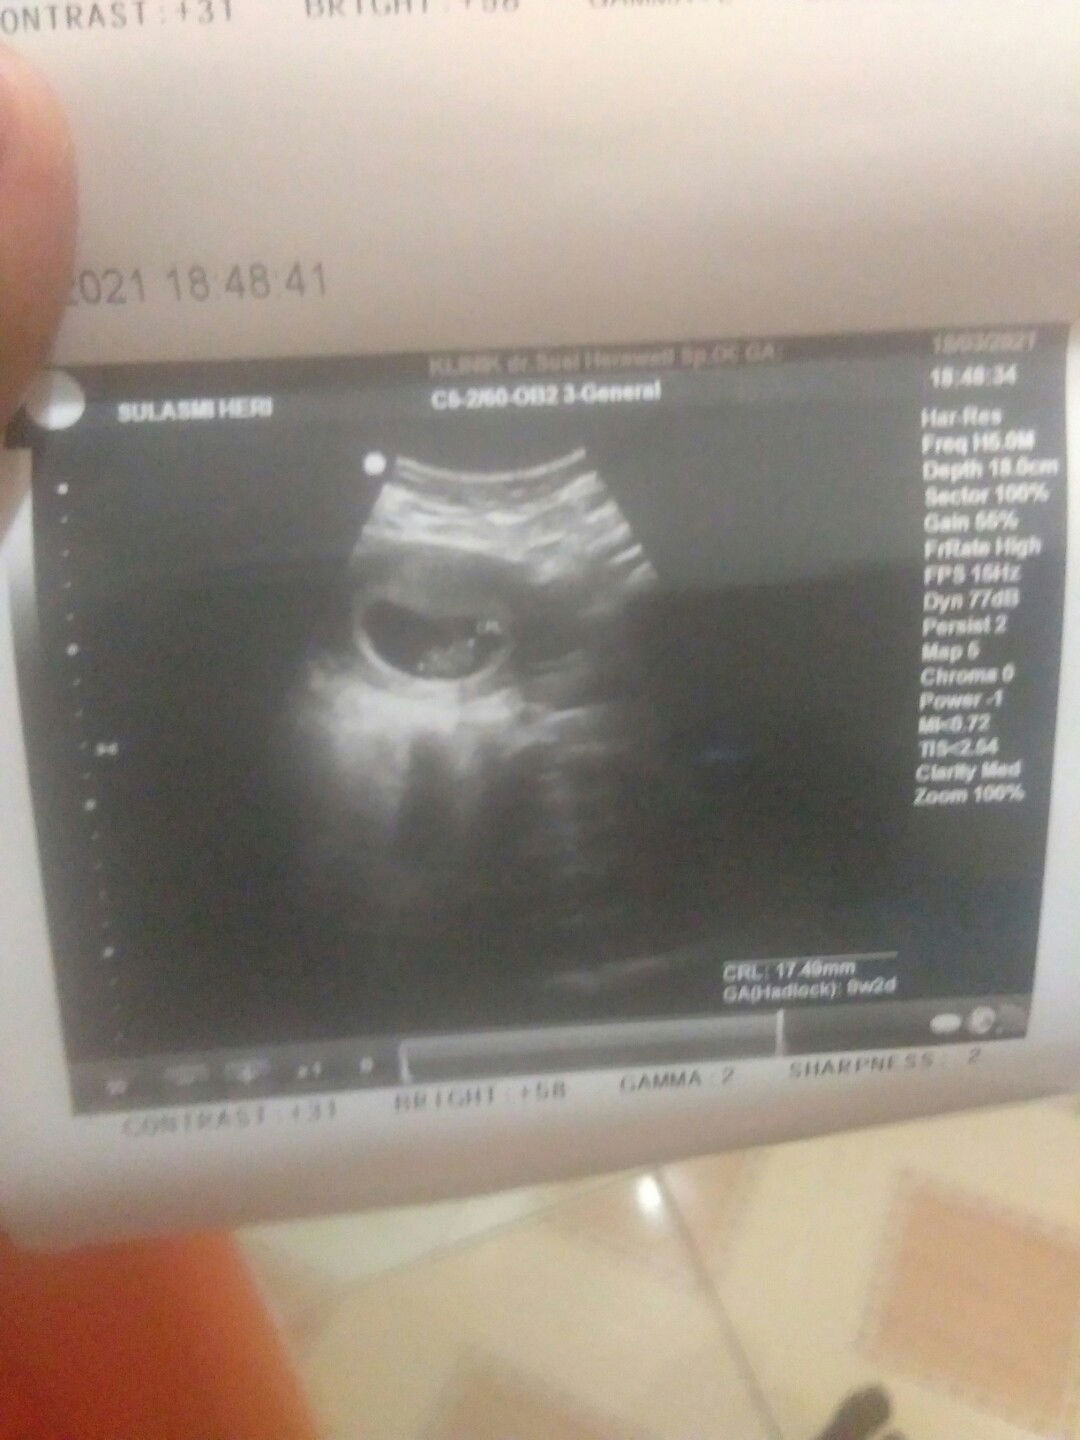

usia 5 minggu, di usg ada gak yang pernah usg di usia segitu??? soalnya janinnya blm kelihatan.

iya mom, masih kantung saja belum terlihat janinnya